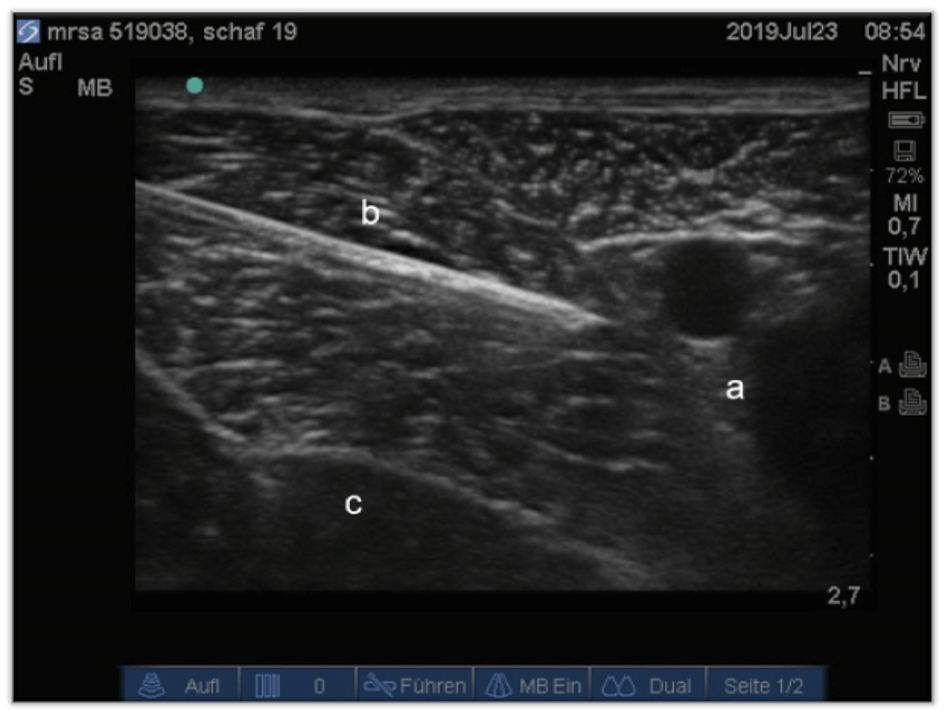

Current anaesthesia protocol at the ARI for orthopaedic hindlimb surgery in sheep includes epidural anaesthesia. Possible complications with an epidural analgesia are urine retention, neural damage, neuritis and temporarily loss of motor function in both hindlimbs. Nevertheless, it is very important to use local analgesia in order to save on anaesthetics and thus reduce their side effects. Therefore, in this study we investigated another protocol for local analgesia: the peripheral nerve block. To provide local analgesia in the operated hind limb we performed an ultrasound-guided block of the sciatic and femoral nerve and compared the analgesic efficacy of the nerve blocks with the epidural analgesia.

Ultrasound-guided peripheral nerve block is a reliable technique in sheep. There was no difference in analgesic effect of epidural and peripheral nerve block. A benefit of the peripheral nerve block is the earlier return to mobility in the recovery period since only the operated leg is motorically restricted.